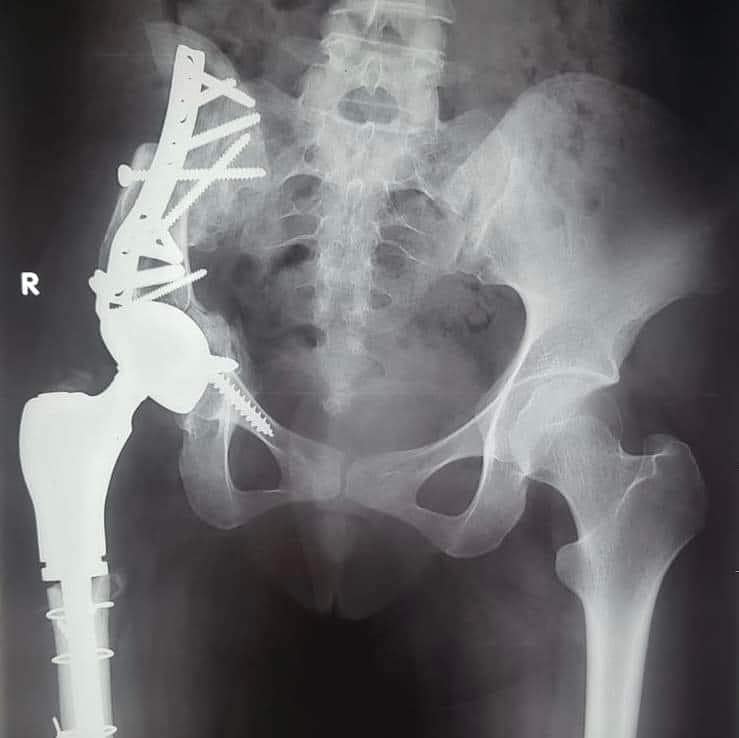

نجح فريق طبي من قسم جراحة العظام بمستشفى أسيوط الجامعي، في إجراء أول جراحة من نوعها؛ لاستئصال ورم من عظمة الآلية، ومفصل الحوض؛ لفتاة تبلغ من العمر الخامسة عشر ، وتركيب مفصل صناعي كامل للحوض؛ مما يمثل إضافة جديدة إلى سجل نجاحات مستشفيات جامعة أسيوط المشهود لها، وتميُّز كوادرها الطبية.

من جانبه، قال الدكتور علاء عطية عميد كلية طب أسيوط ورئيس مجلس إدارة المستشفيات الجامعية: إن العملية الجراحية التي تم إجراؤها كانت على جانب كبير من الخطورة، مبيناً أنه تم إجراء عملية إزالة للورم، واستئصال العظم المصاب بالسرطان، ونقل الجزء العلوي من عظمة الفخذ؛ لتحل محل عظمة الآلية.

وأوضح الدكتور عمرو السيد علي أستاذ جراحة العظام ، واستشاري الجراحات الميكروسكوبية بجامعة أسيوط ، أن المريضة تبلغ من العمر 15 عامًا ، وكانت تعاني من وجود ورم في عظمة الآلية، ومفصل الحوض؛ مشيرًا إلى إجراء العملية الجراحية على مرحلتين في إطار زمني 3 شهور ؛ لتجنب البتر؛ حيث تم في المرحلة الأولي إزالة الورم من عظمة الآلية، ونقل الجزء العلوي من عظمة الفخذ ؛ لتحل محل عظمة الآلية.

وأوضح الدكتور محمد مهران أستاذ جراحة العظام المساعد، واستشاري جراحات تغيير المفاصل الصناعية بجامعة أسيوط، أنه تم- بعد إجراء الفحوصات الطبية- تركيب مفصل صناعي كامل ذي مواصفات خاصة للحوض، وذلك دون اللجوء لتثبيت المفصل، ولتجنب البتر لهذا الطرف؛ مشيرًا إلى نجاح العملية، واستقرار الحالة الصحية للمريضة، وتمت متابعتها؛ لحين عودة حركة المريضة لصورتها الطبيعية، ومشيرا في الوقت نفسه، أنه تم نشر العملية الجراحية عالميًا: في مجلة علمية متخصصة للحالات الصعبة؛ بمساعدة الدكتور أحمد عادل خليفة مدرس جراحة العظام بكلية طب قنا- جامعة جنوب الوادي.